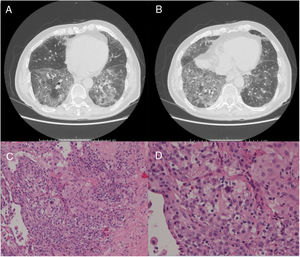

A 79-year-old man, a non-smoker and who had a history of atrial fibrillation, was treated with amiodarone 400mg daily for 3 years. During the last 2 months of treatment, he was presented with exertional dyspnea and dry cough. Respiratory function tests revealed a restrictive ventilatory pattern with a moderate reduction in carbon dioxide lung diffusion (DLCO) (14.3mL/min/mmHg, 55% of predicted value). Chest computed tomography (CT) showed bilateral, peripheral, predominantly basal ground-glass and reticular opacities consistent with a NSIP radiological pattern (Fig. 1, panels A and B). The bronchoalveolar lavage showed a significant amount of foamy macrophages. Transbronchial lung biopsy of the right lower lobe was performed and the histological examination revealed the presence of septal widening with type II pneumocytes hyperplasia, areas of organized interstitial fibrosis with sporadic fibrinous exudates, fibroblasts and collagen deposition next to aggregates of inflammatory cells and considerable amount of foamy histiocytes. These findings were consistent with a diagnosis of APT (Fig. 1, panels C and D). Other etiologies of interstitial lung disease (ILD) were carefully ruled out. Amiodarone was suspended while prednisone 40mg daily and oral anticoagulants were given, with rapid clinical and functional recovery. At 40 days, ground-glass and reticular opacities had almost completely resolved on CT scan while two soft-tissue nodules of 25 and 11mm, respectively, were identified in the right costophrenic sulcus (Fig. 2, panels A and B). Both lesions presented elevated density on CT scan images with Hounsfield Unit (HU) values ranging from 46 to 50. The patient underwent a new bronchoscopy with bronchoalveolar lavage of the right lower lobe, but microbiological and cytological investigations were unremarkable. A tuberculin skin test and blood serological markers for autoimmunity, inflammatory and infectious disease were also performed with negative results. Moreover a supplemental investigation was conducted excluding the onset of new drug treatment, trauma or exposure to environmental agents. Given their rapid onset, the elevated HU values and the exclusion of other coherent etiologies, the nodules were interpreted as an unusual subacute manifestation of APT. As physical insult to pulmonary parenchyma is known to increase susceptibility to toxicity even if low dose amiodarone treatment is used,1 surgical lung biopsy was not performed and radiological follow-up was started. At 18 months, follow-up CT showed a considerable reduction in the size of both lung nodules (Fig. 2, panels C and D) and the clinical condition of the patient was unremarkable.

(Panels A and B) CT scan images showing the resolution of the ground-glass and reticular opacities after amiodarone withdrawal and the onset of two large nodules of 25mm and 11mm, respectively, which ensued in the right costophrenic sulcus. (Panels C and D) Follow-up CT images showing a substantial reduction in size of the right costophrenic nodules 18 months after amiodarone withdrawal.